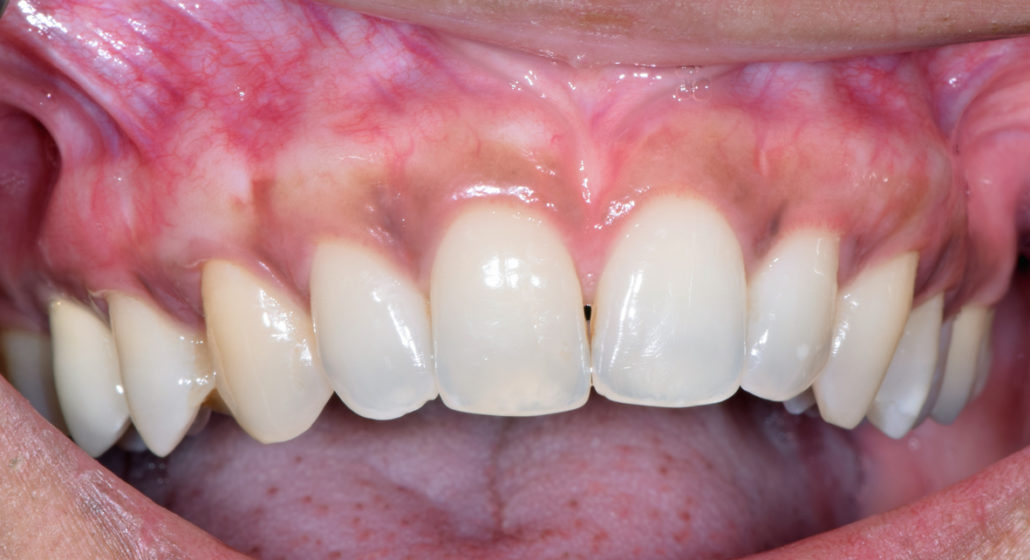

La patiente a été adressée au cabinet par son dentiste traitant pour une solution de remplacement de son bridge maxillaire en fin de vie. Une solution implantaire lui a été proposée pour la réhabilitation de sa mâchoire soit les extractions des dents, mise en place des implants avec aménagement osseux, le tout lors de la même intervention sous sédation vigile. Un Bridge fixe implantaire provisoire et esthétique a été placé 48 heures après l’intervention. Cette prothèse restera en bouche au moins 6 mois pour valider les implants, l’esthétique et la fonction avant de passer aux empreintes pour la prothèse finale (bridge céramique) qui sera totalement adaptée et personnalisée à la demande de la patiente.